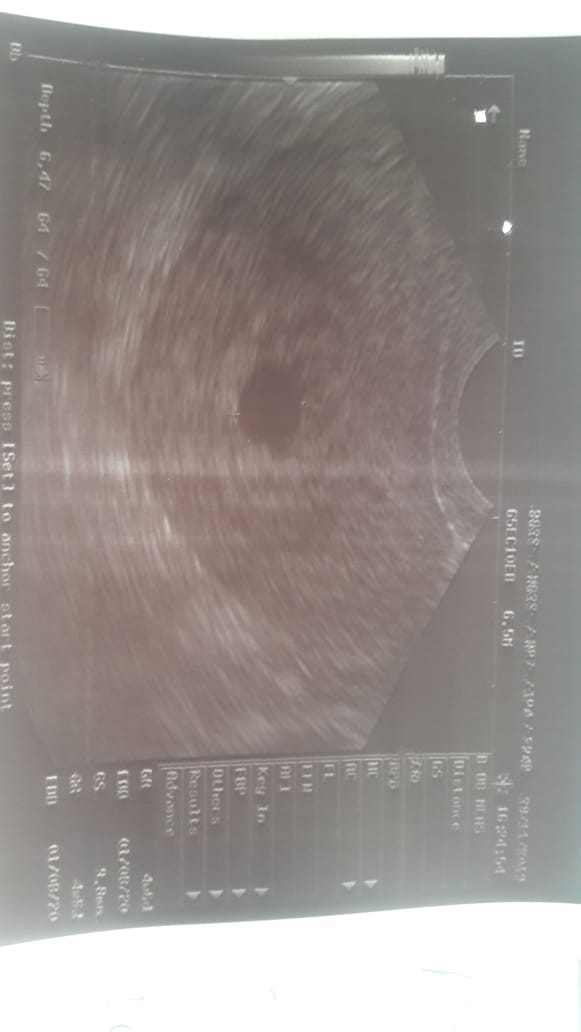

She is married since march. And first time she conceived in may but she had miscarriage after 1 month. Now again she is pregnant. And her last periods date is 6 October. There is a sake scene in the ultrasound report but no baby or baby’s heart is seen. Her gynaecologist suggested her dephaston and folic acid. And told her complete bed rest. I will post the report and please guide me what should she do?

- dear there might be hormonal imbalance history and at present could be date discrepency or not enough hormonal support for pregnancy .

- resscan after 10 days ,report immediately to Gynae if Symmptoms lie pain or bleeding appear.